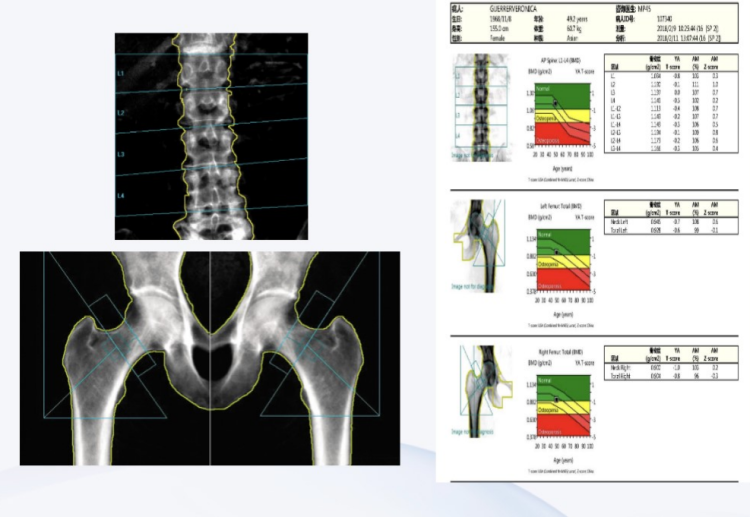

听了医生的这些解释,张阿姨愉快地接受了“再次”检测骨密度的建议。张阿姨在核医学科做完骨密度检查,拿着DXA骨密度报告回来了。医师根据张阿姨骨密度检查报告的T值诊断其骨质疏松并给出了接下来的诊疗方案。

T值是指与健康青年的骨密度相比,受测试者骨密度的变化情况,其用于表示绝经后妇女和大于50岁男性的骨密度水平。依据世界卫生组织推荐的标准,T值≥-1属于正常范围,-1~-2.5属于骨量低下,≤-2.5为骨质疏松。